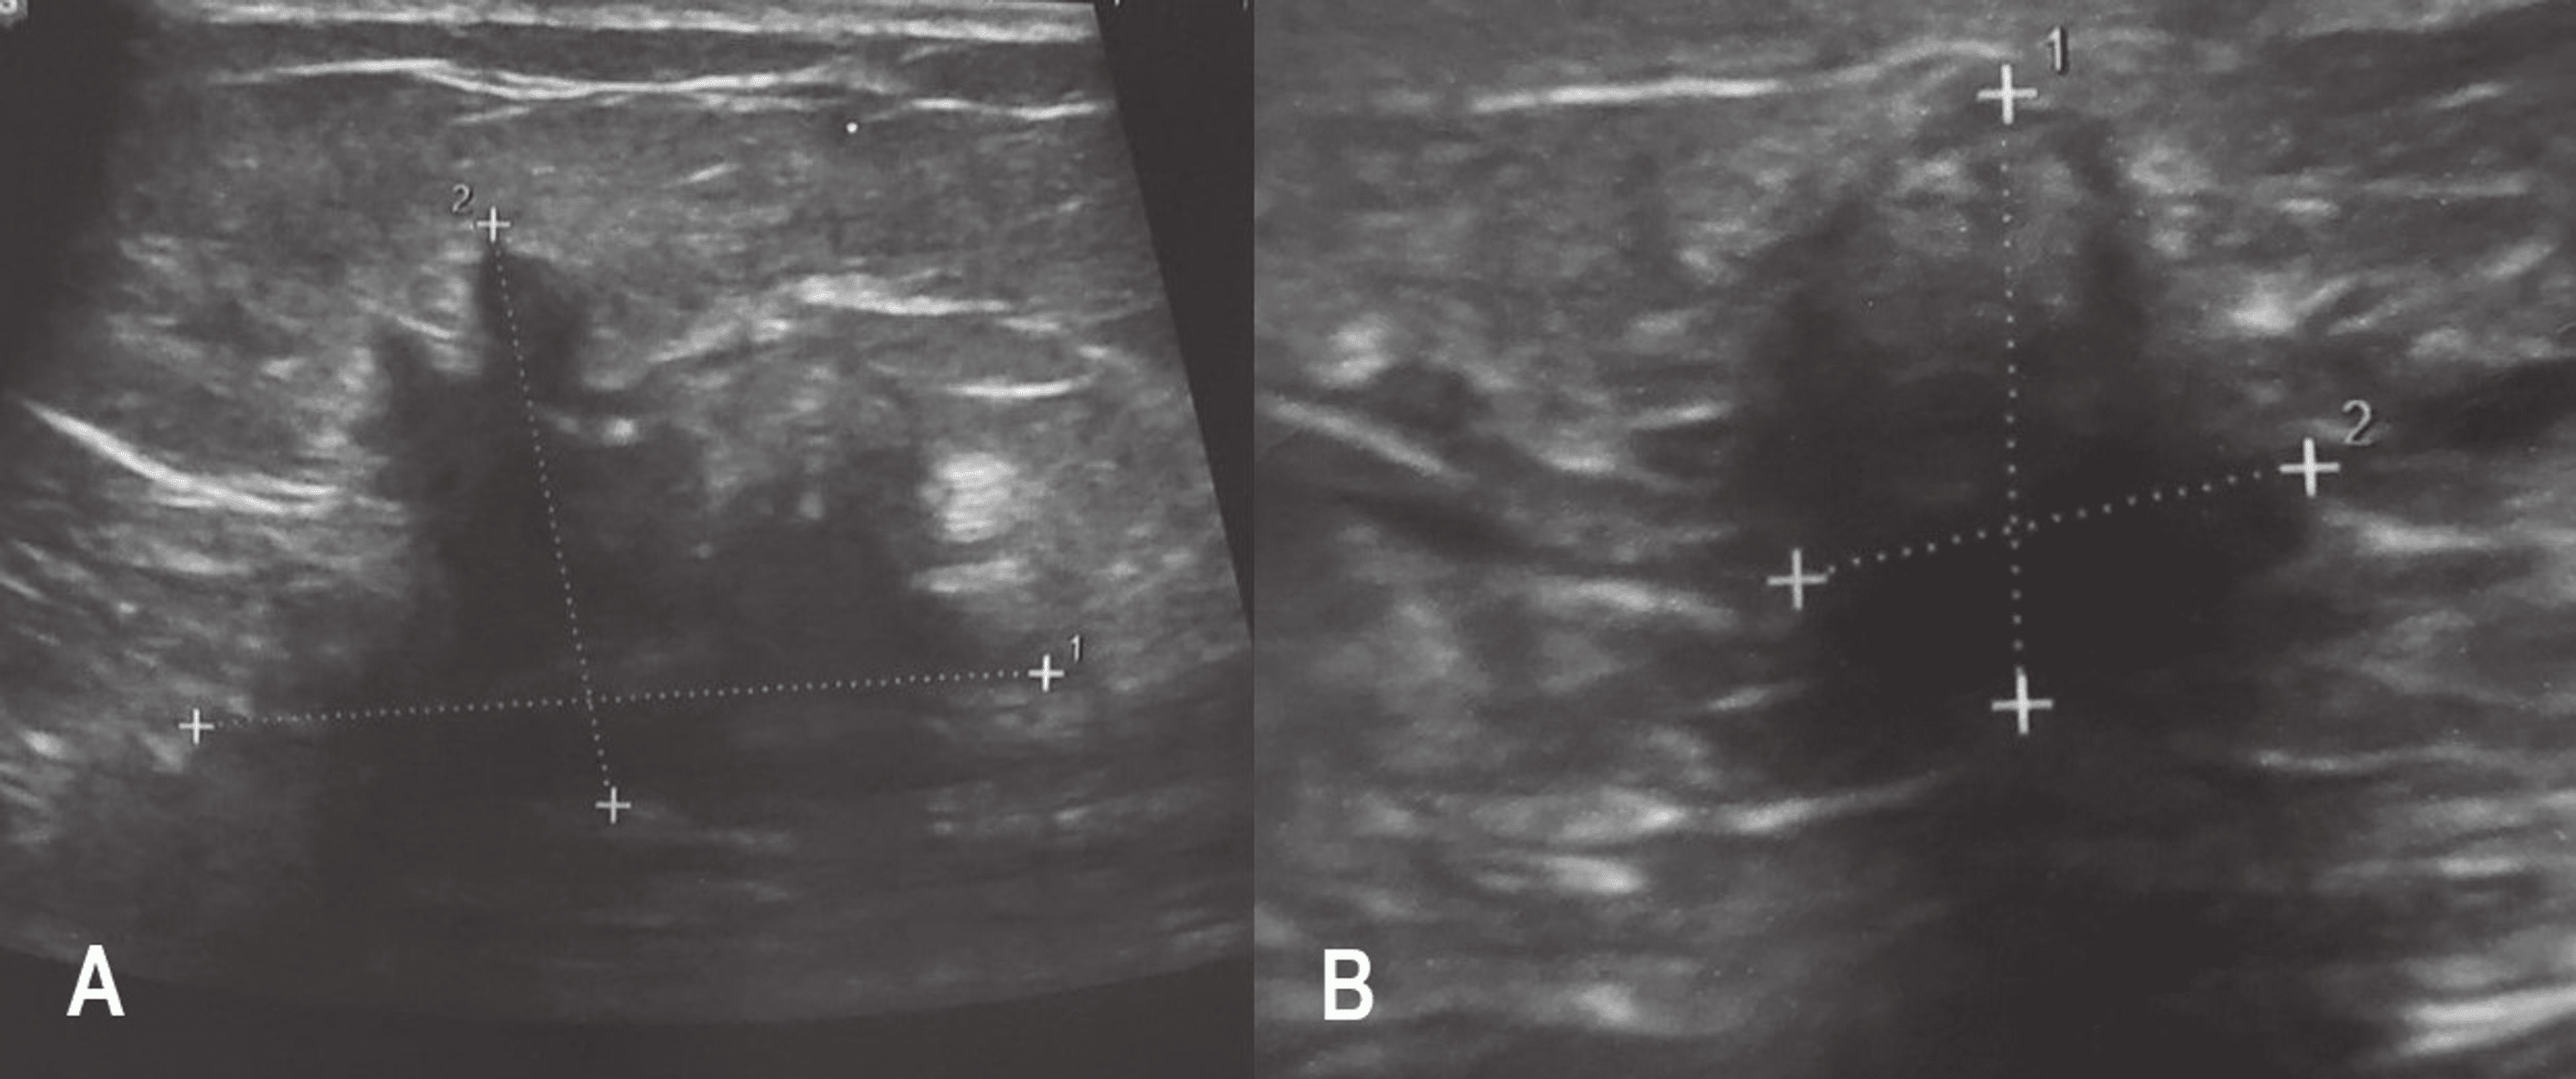

Breast ultrasound demonstrating an irregular hypoechoic illdefined Spiculated Mass Ultrasound After chemotherapy the tumor is not visible on the mammogram. This imaging finding was classified. The most commonly observed mammographic appearance is that of a spiculated mass, but asymmetric density and architectural. Ultrasound demonstrated a 37 mm mass with indistinct and angular margins and shadowing. Spiculated masses commonly produce acoustic shadowing as a result. On ultrasound, spiculated masses shown on. Spiculated Mass Ultrasound.

Ultrasound revealing multiple irregularly marginated, spiculated Spiculated Mass Ultrasound Spiculated masses commonly produce acoustic shadowing as a result. The most commonly observed mammographic appearance is that of a spiculated mass, but asymmetric density and architectural. This imaging finding was classified. Spiculated lesions, a term often used in medical imaging, refer to abnormal growths or areas in the body that display a spiky. On ultrasound, spiculated masses shown on mammograms. Spiculated Mass Ultrasound.

Right breast ultrasound image showing a hypoechoic, attenuating mass Spiculated Mass Ultrasound After chemotherapy the tumor is not visible on the mammogram. This imaging finding was classified. Spiculated lesions, a term often used in medical imaging, refer to abnormal growths or areas in the body that display a spiky. Ultrasound demonstrated a 37 mm mass with indistinct and angular margins and shadowing. On ultrasound, spiculated masses shown on mammograms may be round,. Spiculated Mass Ultrasound.